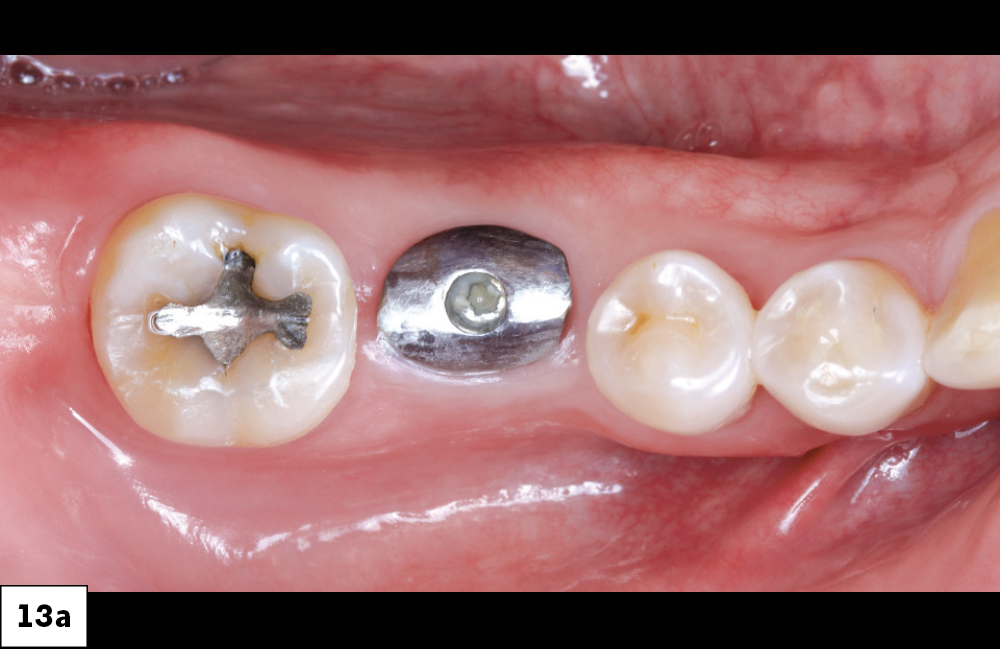

Follow Up Image of the Implant Site with Healing Abutment

Removed Healing Abutment Revealing Well-Contoured Implant Site

Figures 13a, 13b: Removal of the custom healing abutment showed that the tissue surrounding the implant site was healthy and well contoured.